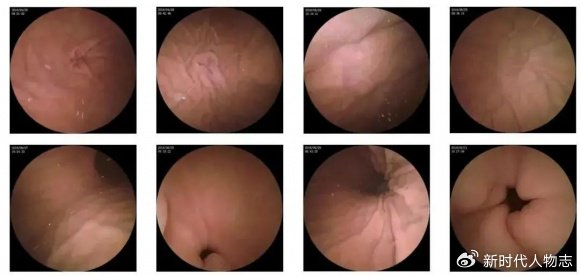

肛門息肉早期圖片展示

(請?jiān)诖颂幉迦敫亻T息肉早期圖片)

圖片展示可以幫助公眾更直觀地了解肛門息肉的外觀和癥狀,請注意,由于個(gè)體差異和拍攝角度等因素,圖片僅供參考,不能作為診斷依據(jù)。